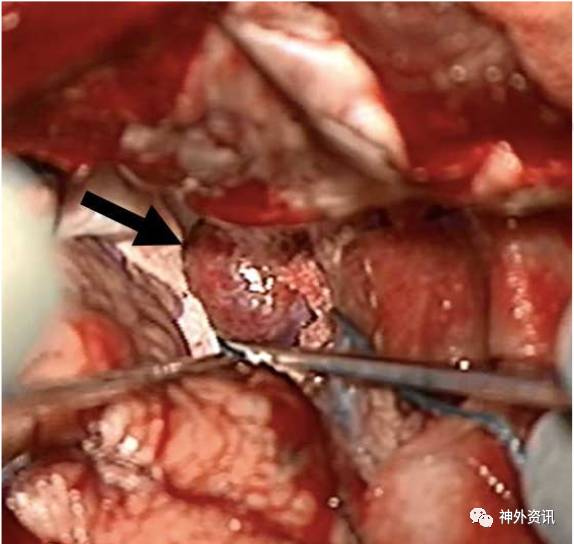

36岁男性患者。因外伤后行影像学检查,意外发现右侧中颅窝占位病变,无临床症状。术前MRI检查显示,右侧前床突一起源于硬脑膜的肿物,T1加权呈低信号,T2加权呈等信号,增强扫描均匀强化,考虑为脑膜瘤。经右侧翼点入路全切除病灶,无术后并发症。术后病理学检查,见病变为扩张、硬化的血管团,间质无神经组织,血管内有血栓形成,符合海绵状血管瘤。

图3. 术中照片可见前床突占位病变,像脑膜瘤;术中分离和切除肿瘤较一般的床突旁脑膜瘤容易。